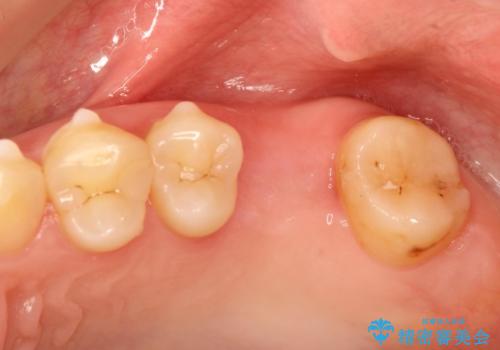

奥歯が割れてしまった! → インプラントによるかみ合わせの回復

- 歯根破折を生じた奥歯を抜歯後、治癒の期間を経てインプラントを埋入